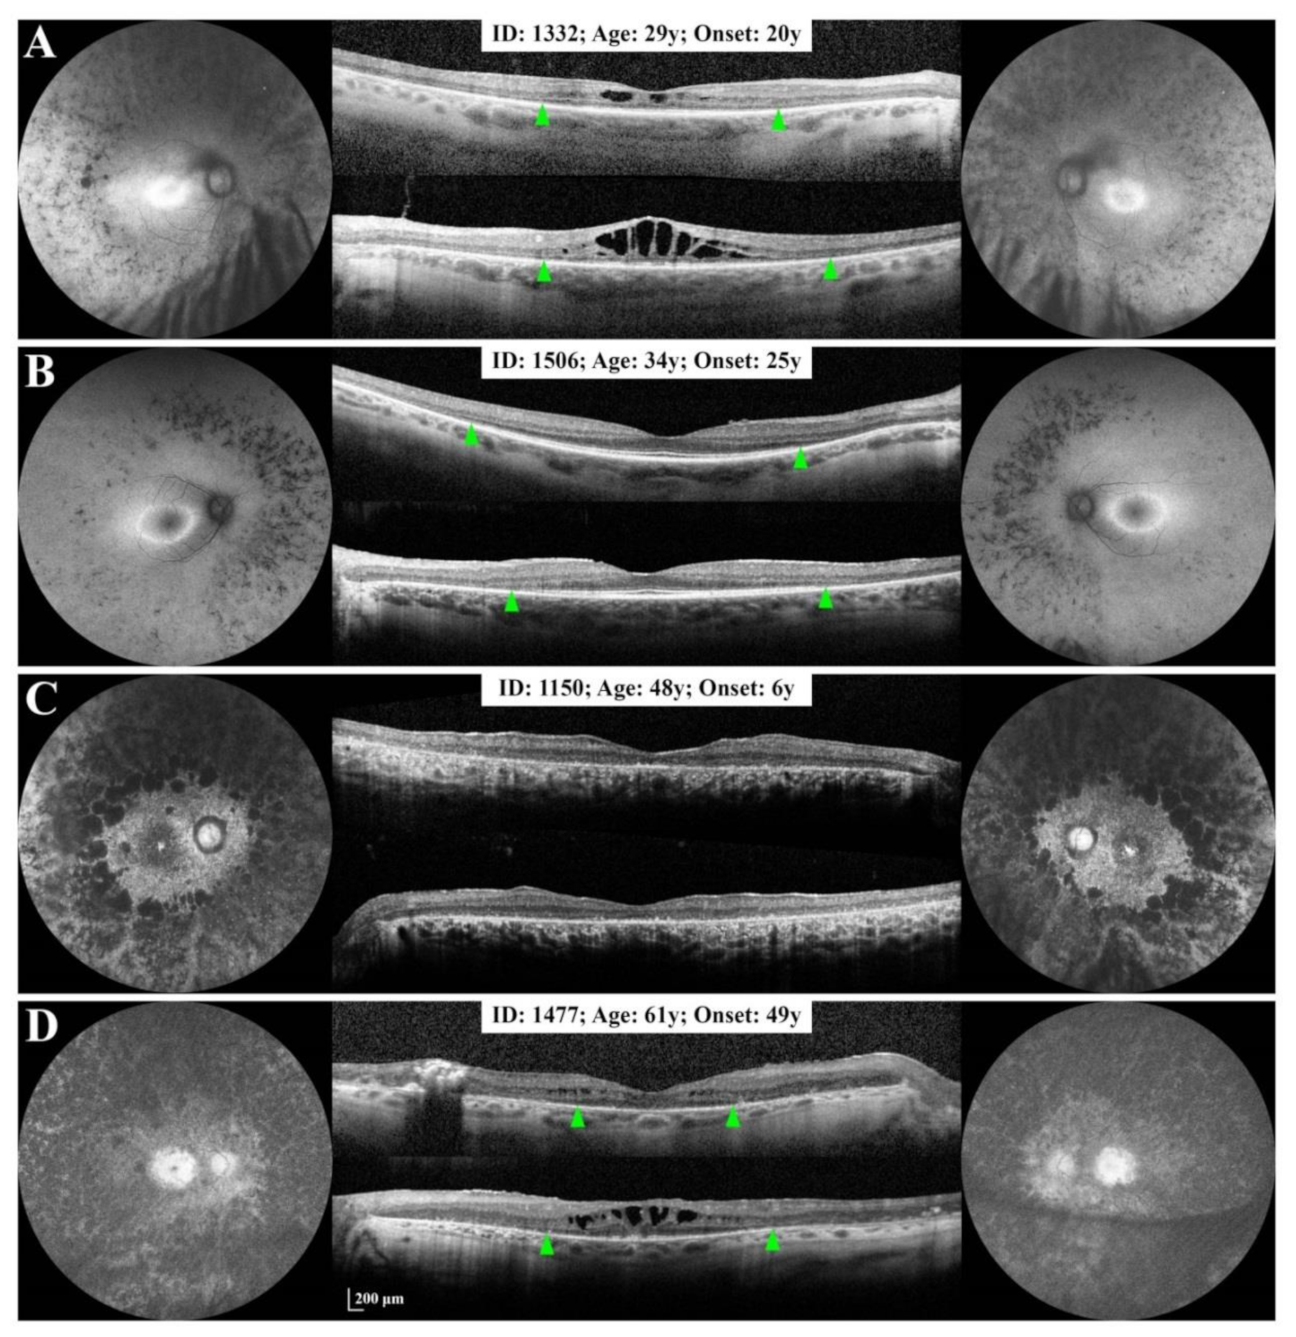

3.2. Baseline Clinical Features

3.2.1. Small Deletion/Deletion-Insertion

3.2.2. Splice Site Mutations

3.2.3. Large Deletions

3.4. Phenotype Patterns